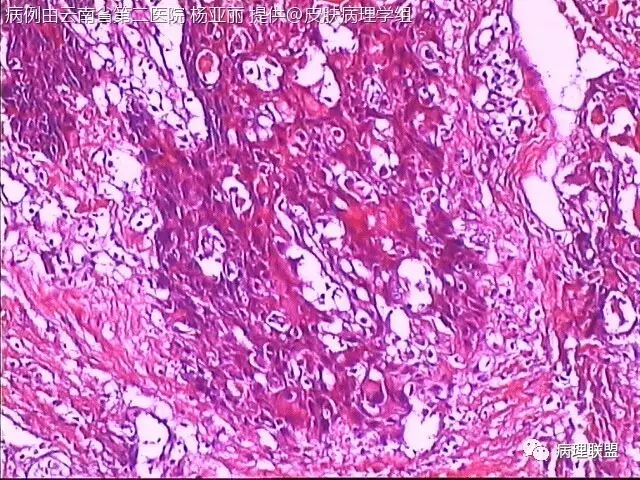

M/53 左手食指包块(皮肤鳞癌VS转移性鳞癌)

请各位老师帮忙看看,男性,53岁,左手食指包块 (病例由云南省第二医院 杨亚丽 提供,致谢!)

@邓永键 谢谢邓主任,据说病人鼻子上有肿瘤才来切的手上的小包块,右手有,左手也有三四个,等我再问问鼻子上的是什么。看着细胞异型不明显,生长方式倒是确实不好。第6图有和表皮的关系,不相连,邓老师,鼻子上的肿瘤确实是鳞癌,这么说来手上的是转移的就很合理了。邓主任真是高,佩服!